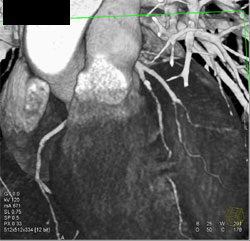

Diseased LAD